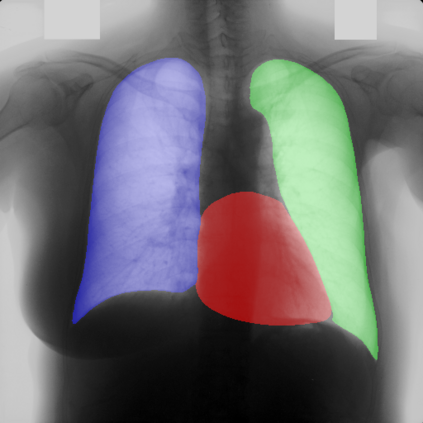

Multi-organ segmentation of X-ray images is of fundamental importance for computer aided diagnosis systems. However, the most advanced semantic segmentation methods rely on deep learning and require a huge amount of labeled images, which are rarely available due to both the high cost of human resources and the time required for labeling. In this paper, we present a novel multi-stage generation algorithm based on Generative Adversarial Networks (GANs) that can produce synthetic images along with their semantic labels and can be used for data augmentation. The main feature of the method is that, unlike other approaches, generation occurs in several stages, which simplifies the procedure and allows it to be used on very small datasets. The method has been evaluated on the segmentation of chest radiographic images, showing promising results. The multistage approach achieves state-of-the-art and, when very few images are used to train the GANs, outperforms the corresponding single-stage approach.